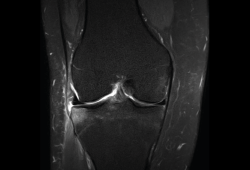

Se consiguen unas imágenes de alta resolución para la valoración de meniscos, ligamentos y tendones. Además, es especialmente útil en las rodillas operadas, lesiones tumorales, evaluación del cartílago y la visualización de los nervios(13).

1. Estudio de las estructuras intraarticulares

Es la prueba no invasiva de elección para valorar las lesiones internas de la rodilla(2). Aunque el estudio por RM es a menudo considerado como la prueba diagnóstica de elección para la detección de alteraciones meniscales, se asocia en ocasiones con errores diagnósticos(16).

1.1. Meniscos

Se identifican como estructuras hipointensas en todas las secuencias, con asta anterior y posterior de morfología triangular.

La RM es la técnica de elección en el diagnóstico de la patología meniscal(17)(Figuras 30, 31, 32, 33, 34 y 35).